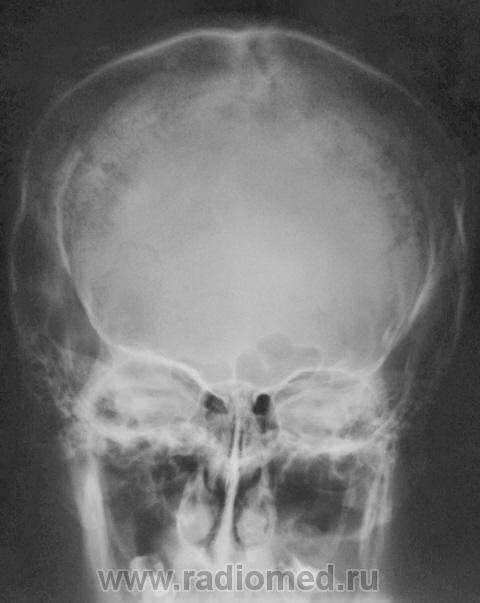

Nela. КТ головного мозга и костей. Гистиоцитоз Х (морфологическая верификация).

Пациент - молодой человек, предъявляет жалобы на головные боли и боли в шее. Болеет с 2002 года.

Гистиоцитоз Х – заболевание ретикулоцитарной системы неизвестной этиологии, морфологически характеризующееся первичной пролиферацией своеобразных гистиоцитов (клеток Лангерганса или клеток Х) и образованием в легких и в других органах и тканях гистиоцитарных гранулем и гранулематозных инфильтратов.

Заболевание относится к системным: гранулемы могут образовываться в различных органах, но наиболее часто поражаются легкие и кости. Заболевают чаще всего люди молодого возраста, между 20 и 40 годами, большей частьюмужчины.

Такое обширное поражение нечасто встречается. Я вижу впервые.

Конечно чаще, но не каждый день. Гистиоцитоз Х или эозинофильная гранулема, или гистиоцитоз из клеток Лангерганса редкое заболевание. Но, думаю, каждый рентгенолог со стажем видел костный гистиоцитоз в костях свода или в позвонке. У нас областное гематологическое отделение, поэтому наверно раз в 1-2 года встречаем.